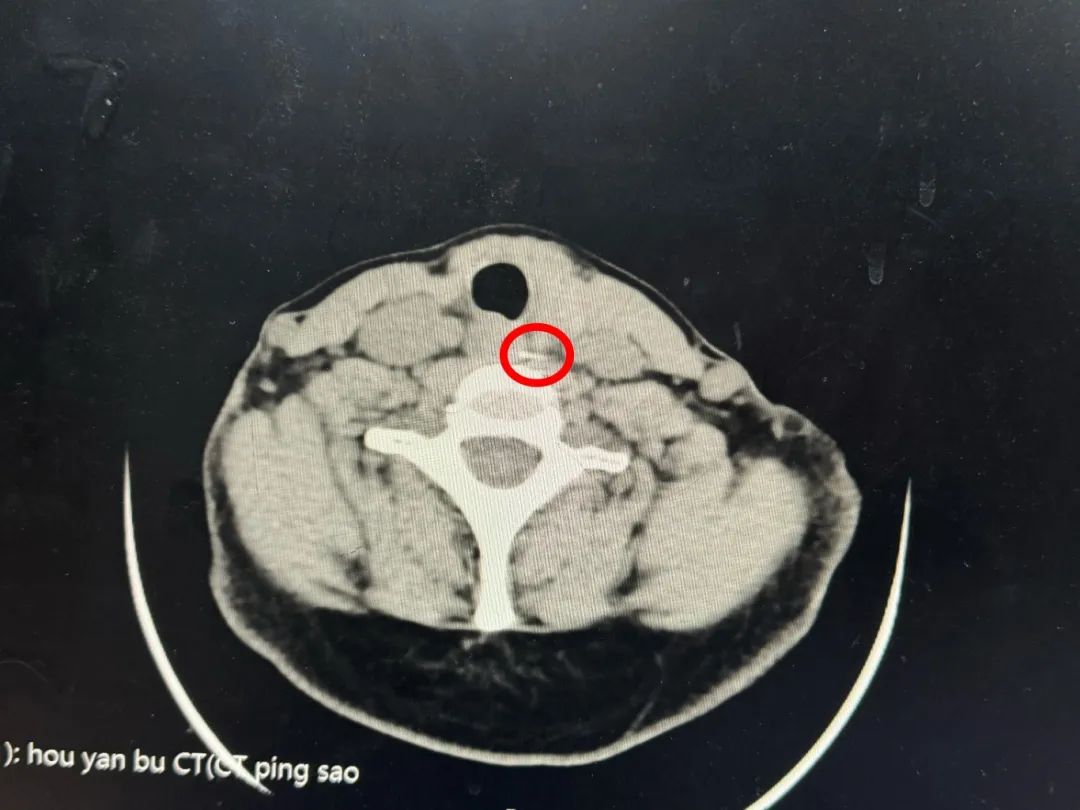

到院后医生根据病情,安排相关检查,发现咽喉部没有异物,CT发现食道有异物,且食道已穿孔,需住院进行治疗。